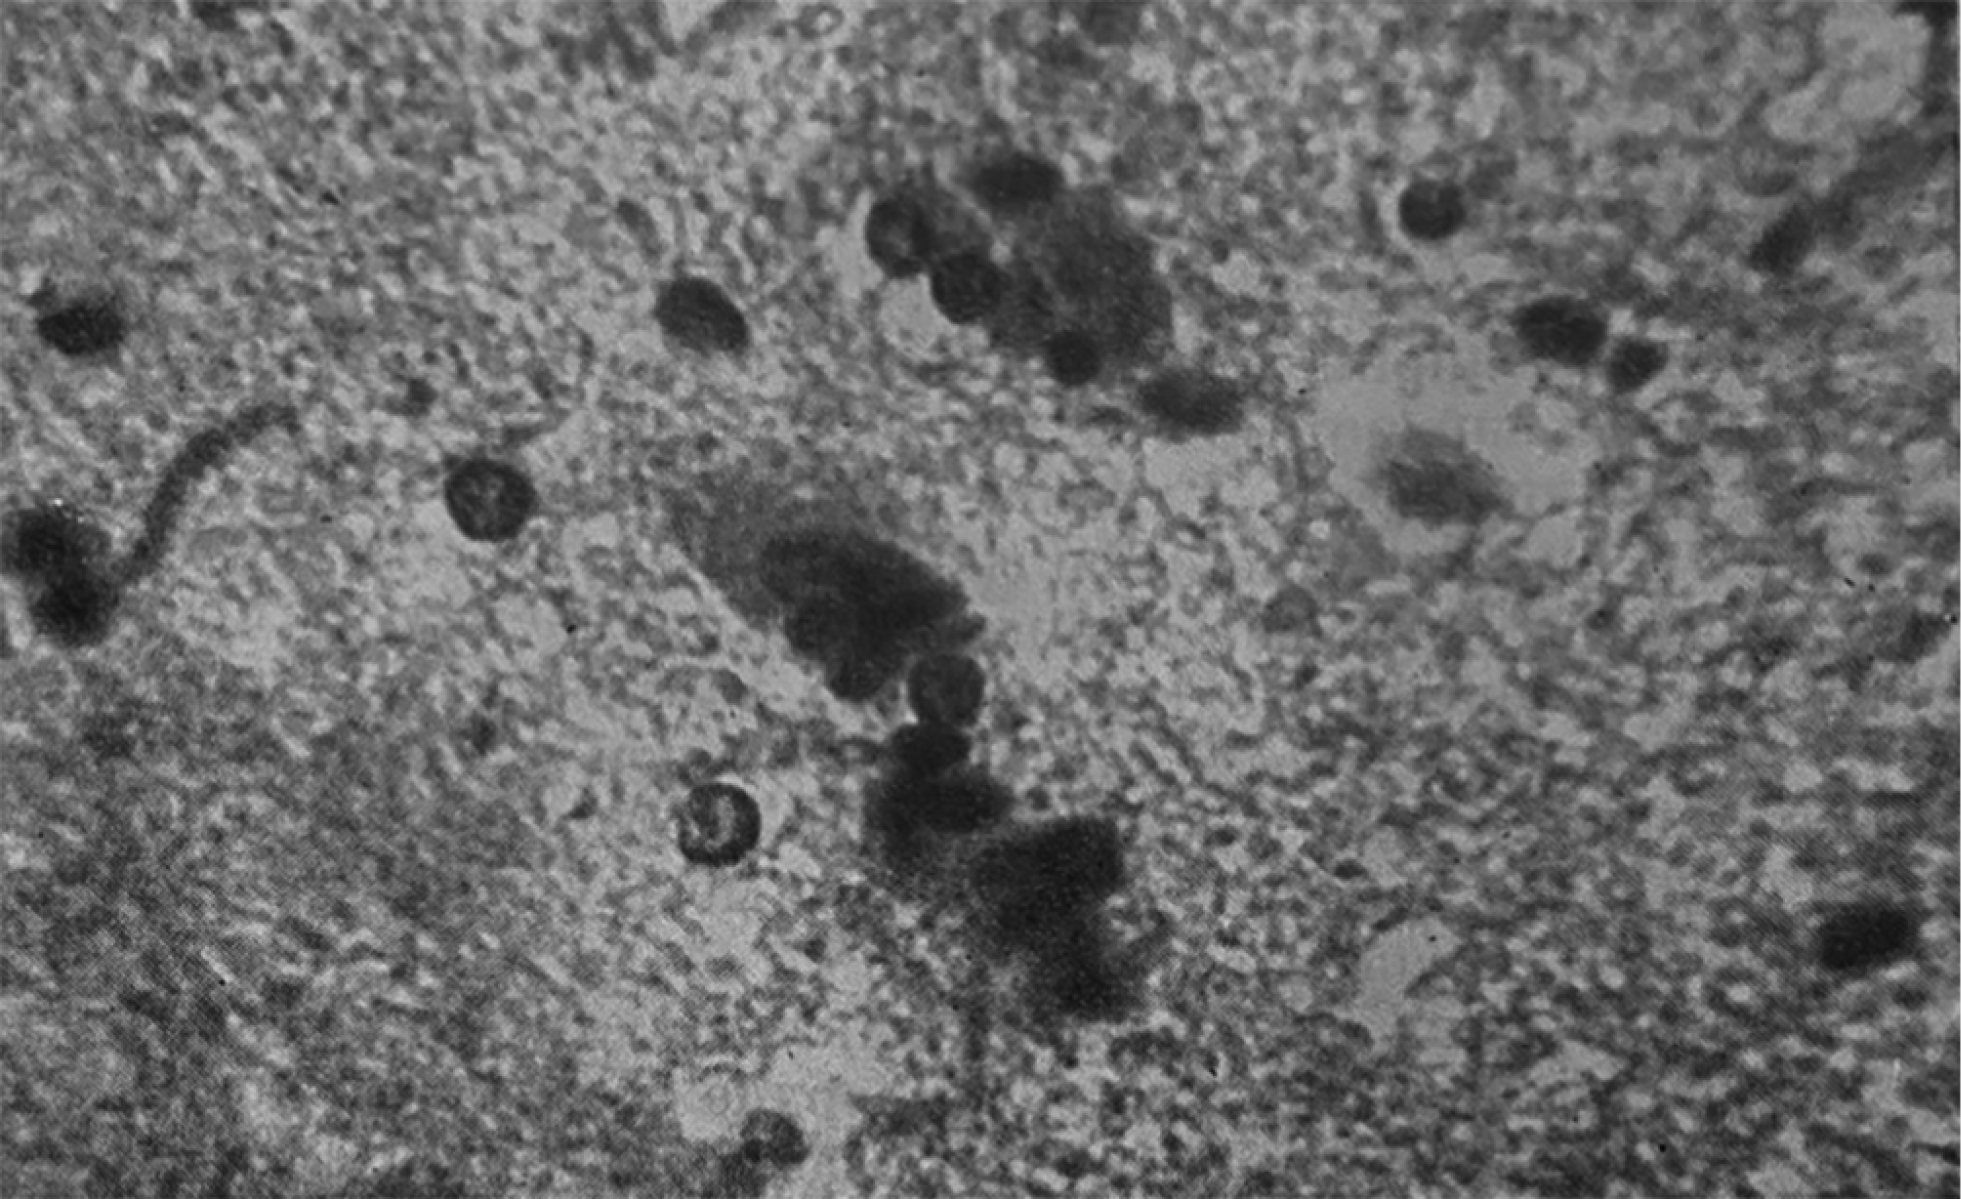

Среди работ Я.Л. Рапопорта по кардиопатологии особое место занимает изучение миокардитов и кардиомиопатий: он создал их систематику и дал клинико-морфологическую характеристику [6]. Он также ввёл в практику понятие реанимационной патологии. Лаборатория патоморфологии, которая располагалась на базе ИССХ АМН СССР, принимала активное участие в изучении пороков сердца, патологии искусственного кровообращения, перфузионных осложнений [3]. В монографии 1972 года [6] совместно с В.И. Бураковским, Г.Г. Гельштейном, Е.И. Степаняном и Г.И. Цукерманом Яков Львович Рапопорт на основе опыта 1300 операций, проведённых с использованием аппарата искусственного кровообращения, привёл первую отечественную классификацию осложнений, развивающихся во время операции с искусственным кровообращением и экстракорпоральной оксигенацией. Он занимался фундаментальными вопросами патоморфологических реакций организма на адекватность перфузии в ходе использования аппарата искусственного кровообращения (рис. 4). Большое значение Я.Л. Рапопорт придавал нарушению сосудистой и клеточной проницаемости как универсальным механизмам в патогенезе расстройств, возникающих в ходе длительного применения искусственного кровообращения. Я.Л. Рапопорт изучил гистологические изображения препаратов, полученных от экспериментальных животных; сосудов микроциркуляторного русла различной локализации: твёрдой мозговой оболочки, брюшины, перикарда, лёгких, миокарда и других. По результатам трёх серий экспериментов профессор Рапопорт и его коллеги пришли к выводу, что невозможно выявить ведущий механизм из аппарата искусственного кровообращения, наиболее значимо влияющий на патоморфологические изменения. Состав перфузата, объёмные скорости перфузии, длительность операции и принципы анестезии — всё в целом влияет на адаптационные изменения организма.

Рис. 4 . Микрофотографии из монографии [6]: a — периваскулярное кровоизлияние в лёгком при перфузии цельной кровью; b — контрактурные изменения пучков кардиомиоцитов.

Fig. 4. Microphotographs from the monograph [6]: a — perivascular hemorrhage in the lung during perfusion with whole blood; b — contracture changes in cardiomyocyte bundles.

Яков Львович Рапопорт предложил морфологическую систематизацию различных форм контрактурных сокращений мышечных пучков миокарда и изучил патологическую анатомию острой сердечной недостаточности [6]. Контрактурная дистрофия в рамках главы об острой сердечной недостаточности вследствие применения аппарата искусственного кровообращения рассматривается им как морфологический субстрат острой сердечной недостаточности (см. рис. 4). Статья Я.Л. Рапопорта и Ю.Г. Тинякова расширила представление об этом состоянии, разделяя некоторые морфологические понятия: в частности, авторы разделили собственно контрактуры, полосы сокращения, фрагментации и зернисто-глыбчатый распад [7].